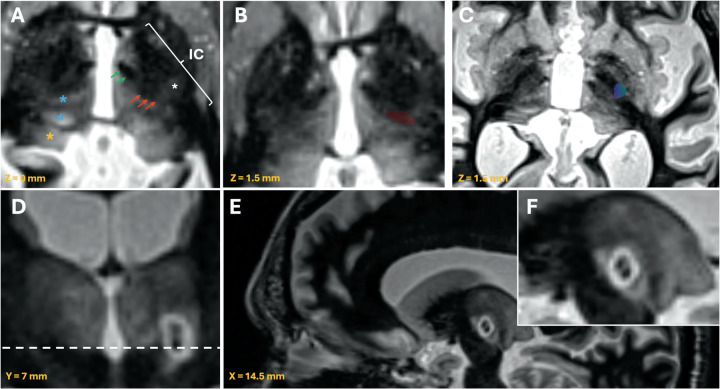

Material and methods: Preoperative and postoperative white matter null (WMn) MR-imaging was employed for direct Vim detection. Essential anatomical landmarks are identified. Dual-lesion conformality was used to adapt to the spatial distribution of the Vim.

Results: Lesions of the Vim were identifiable using the postoperative WMn MRI sequence. The direct visualization of the Vim usually avoids extension into the internal capsule and the sensory thalamic nucleus. Sagittal imaging confirmed the dual-lesion conformational strategy which conforms to the antero-superior orientation of the Vim.